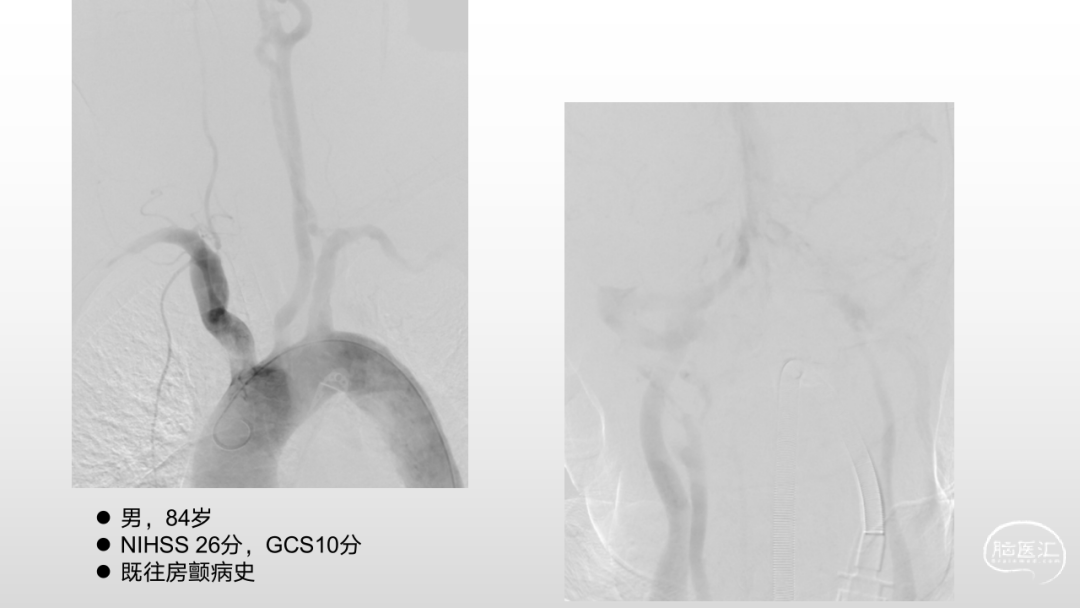

取之有道·第54期|李子付:Flowgate2取栓应用